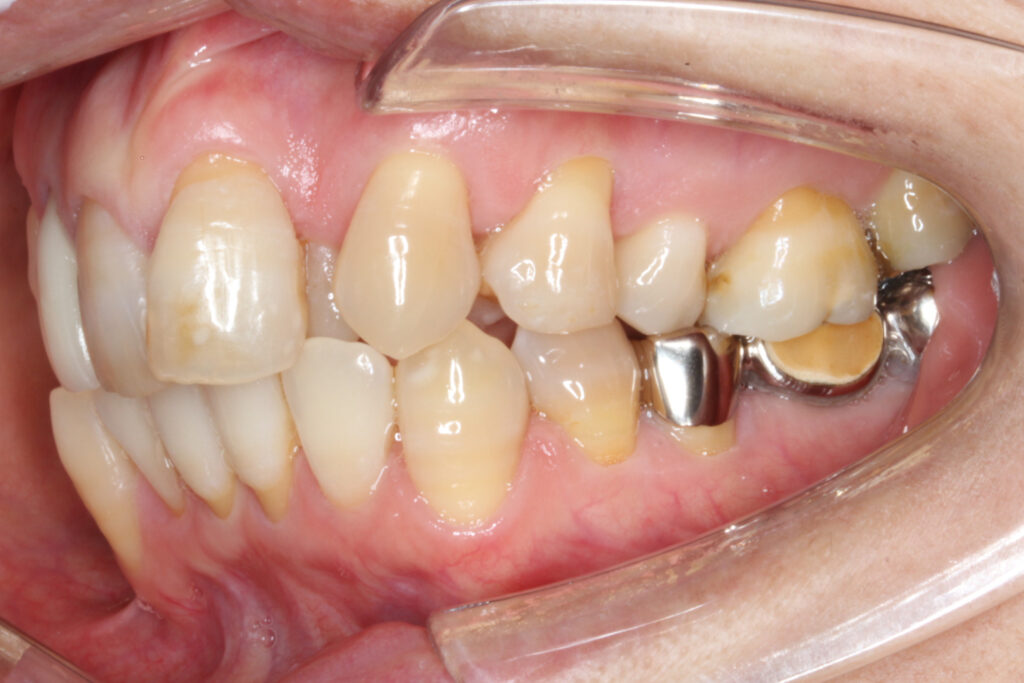

治療はインビザラインにて行い、スペース不足の著しい上顎左側のみ4番を抜歯し、

歯並びの中心を合わせるために、上顎右側は全体的に後方へ移動させる方針としました。

治療期間は19ヶ月という大変短い期間で終了することができました。

治療後は、上下顎の中心が一致し、でこぼこが解消されて前歯の印象が良くなりました。

また、ブリッジの部分も無事に壊さずに、上顎の歯と問題なく噛み合っています。

After